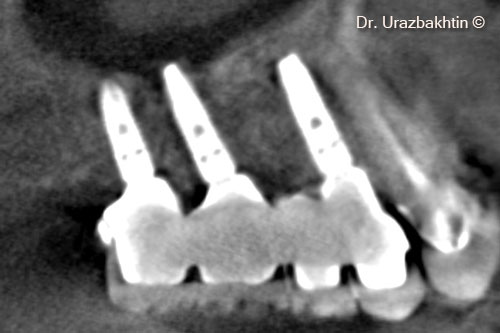

X-ray 3 years post-op